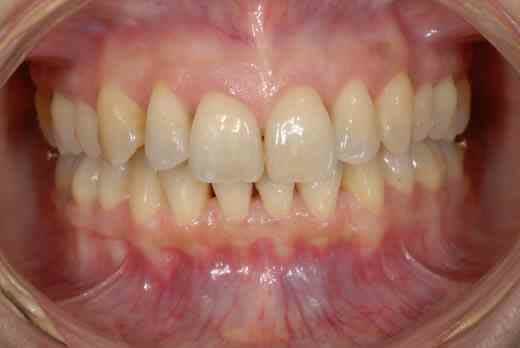

voilà quelques roros et un an plus tard...

J’aurais tendance à penser comme val en ce qui concerne ta classe II, mais ce qui me turlupine le plus dans ton cas, Doc, c’est la différence de hauteur des collets des incisives apparue pendant le traitement.

La ligne des collets ne semble pas trop mauvaise sur la photo d’avril, ce n’est malheureusement plus le cas sur celle de décembre, où le collet de la 11 apparaît plus bas que celui de la 12.

Par rapport à ta lèvre supérieure, qu’est-ce que cela donne dans le sourire ?

(ça se voit pas dans le sourire...)

suis pas ortho mais c'est plutôt moins pire qu'au début du traitement donc dans 2ans c'est top

un beau chtit sourire pour vous, héhé :-P